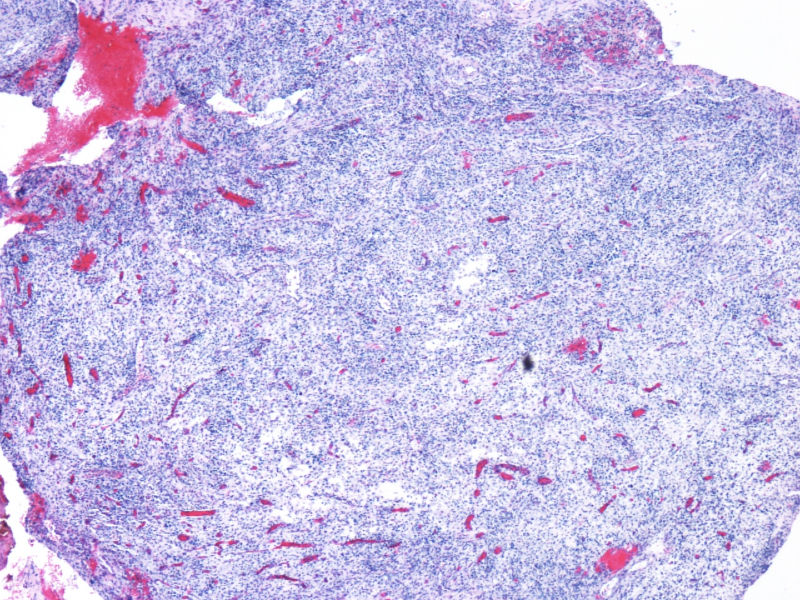

最终诊断为:ALK阳性的间变性大细胞淋巴瘤,淋巴组织细胞变异型。

拿出来的目的:本例始发于骨骼,临床提示脓肿或骨髓瘤,ALK阳性但EMA阴性,细胞毒只有一个标记阳性,本例CD4不阳性。因为CD30和CD15均有非肿瘤细胞阳性的情况,所以对于这个骨骼病例,细胞少而退变,因此最初没有信心诊断,但ALK一般不在非肿瘤细胞内阳性表达,所以最终还是诊断了ALCL。